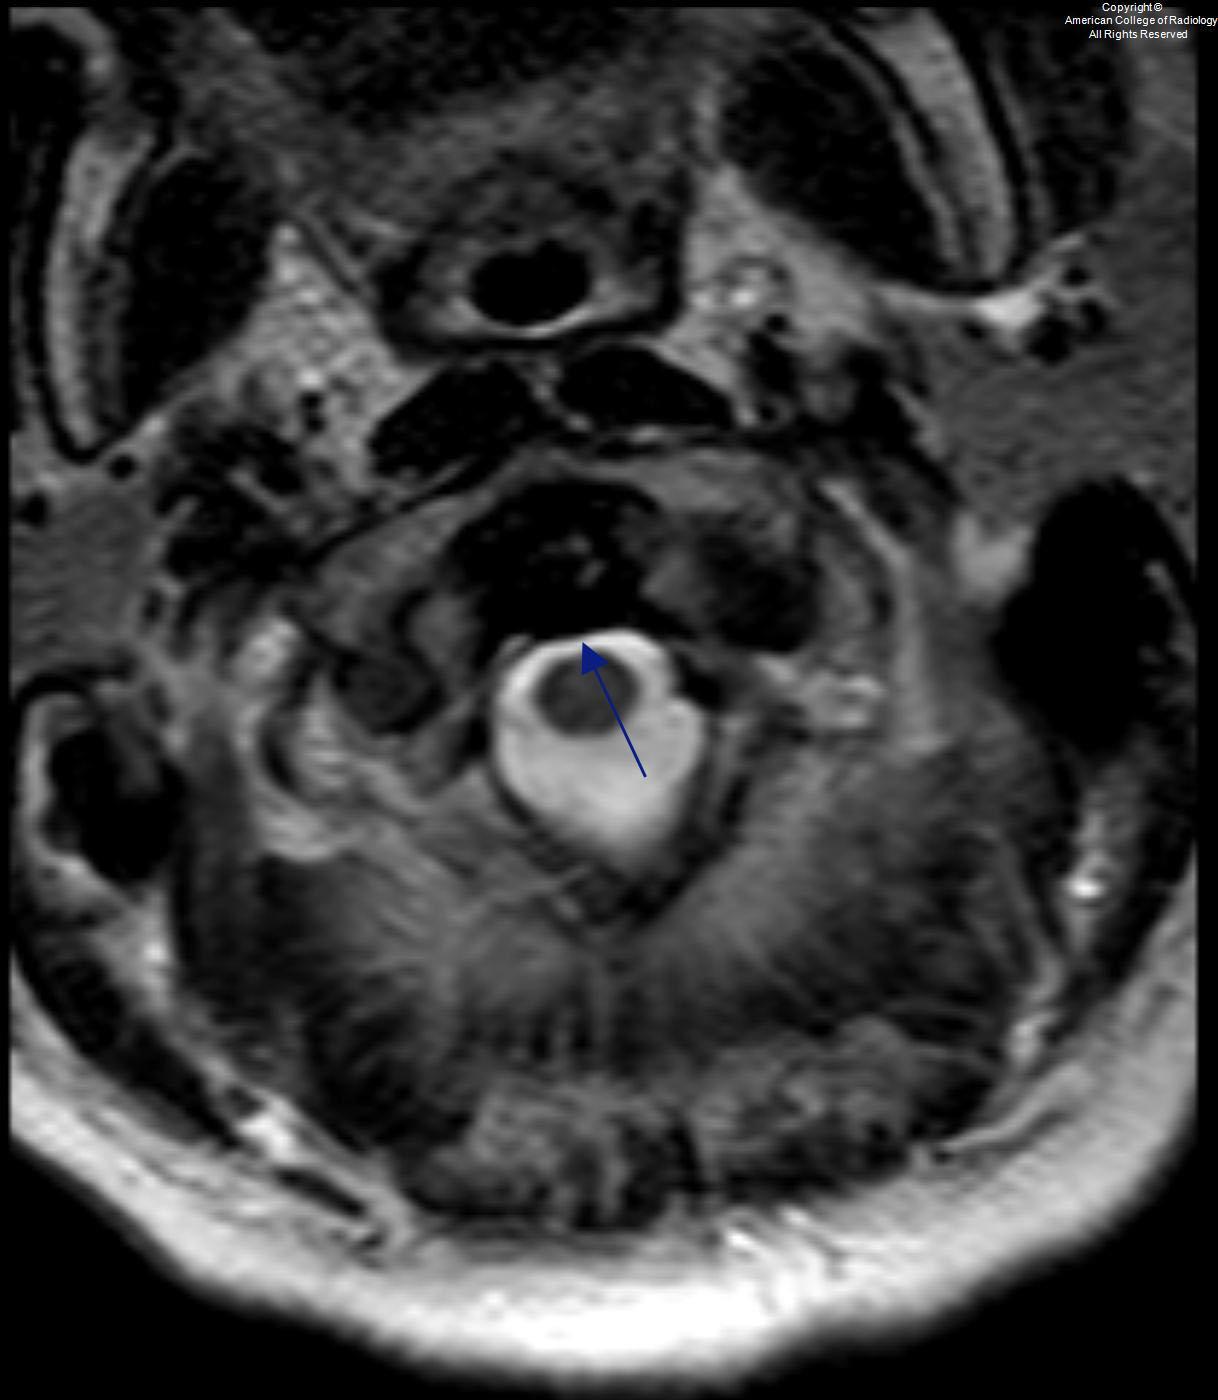

Intact Transverse Ligament C1/2

Torn Transverse Ligament C1/2

Transverse Ligament

• The transverse ligament of the atlas is a thick, strong band, which arches across the ring of the atlas, and retains the odontoid process in contact with the anterior arch.

• In Jefferson’s fracture - C1 fracture

• if transverse ligament is intact - stable - conservative management

• if transverse ligament is disrupted - unstable fracture - surgical management